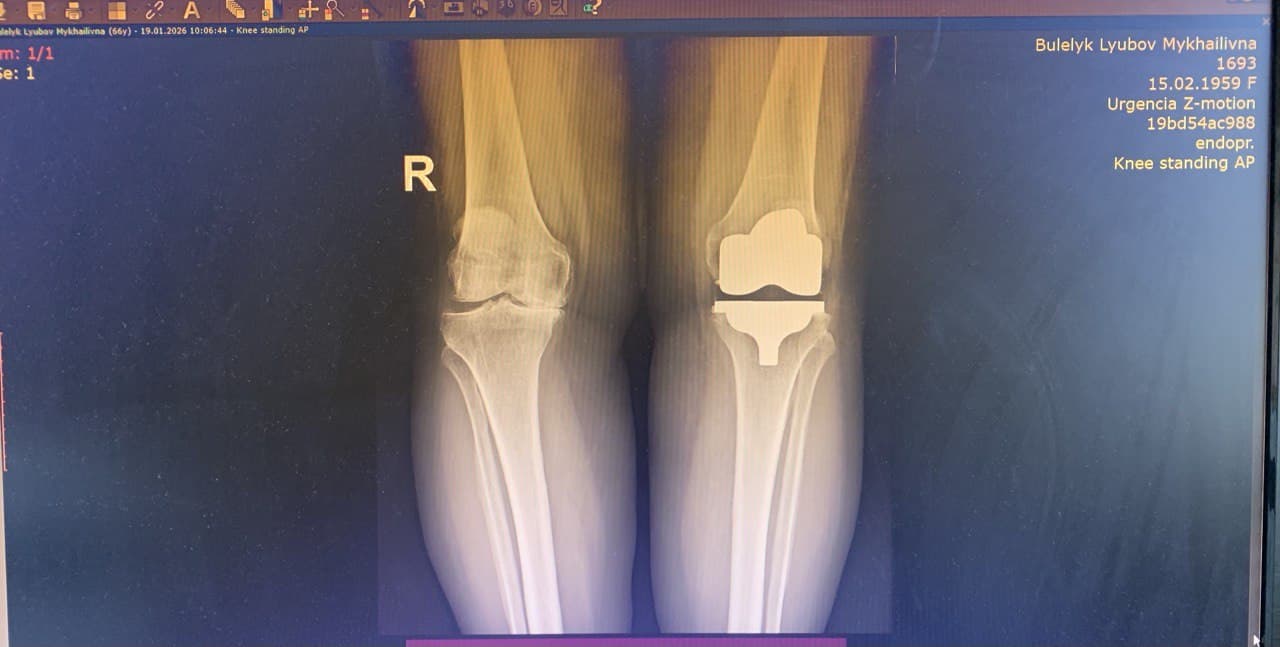

Однією з пацієнток, якій виконали операцію з використанням кінематичного методу, стала Любов Булелик із села Заріччя  Делятинської громади. Жінка розповідає, що проблеми з колінами тривали не один рік, однак значно посилилися після перенесеного коронавірусу. У 2023 році після обстежень їй підтвердили виражений артроз і рекомендували операцію. Спершу вона намагалася лікуватися консервативно.

За словами Андрія Шийки, пацієнтка мала виражений артроз із контрактурою колінного суглоба та суттєвим обмеженням рухів. Без оперативного втручання це означало би «біль, обмеження рухів: не могла б ходити, працювати». Зараз пацієнтка успішно проходить реабілітацію.